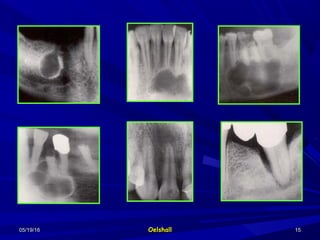

3- Changes inside the lesion.3- Changes inside the lesion.

1- Unilocular.1- Unilocular.

2-Multilocular.2-Multilocular.

3-Multiple and separate.3-Multiple and separate.